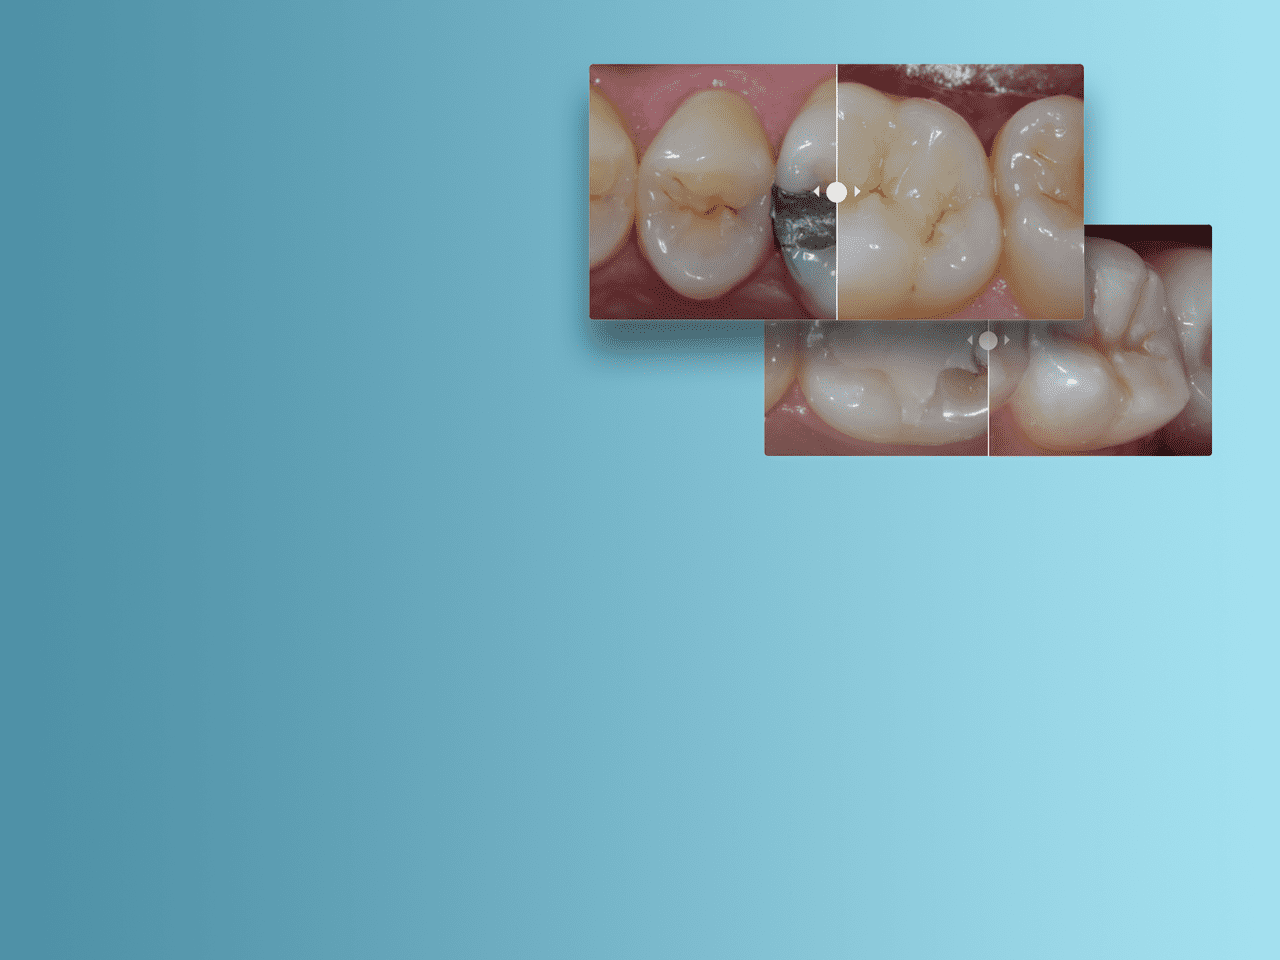

Клинические случаи II класса

В рамках решения для реставраций по II классу компания Dentsply Sirona предлагает инструменты и методы, необходимые для того, чтобы успешно выполнить процедуру и обеспечить максимальную удовлетворенность пациентов.